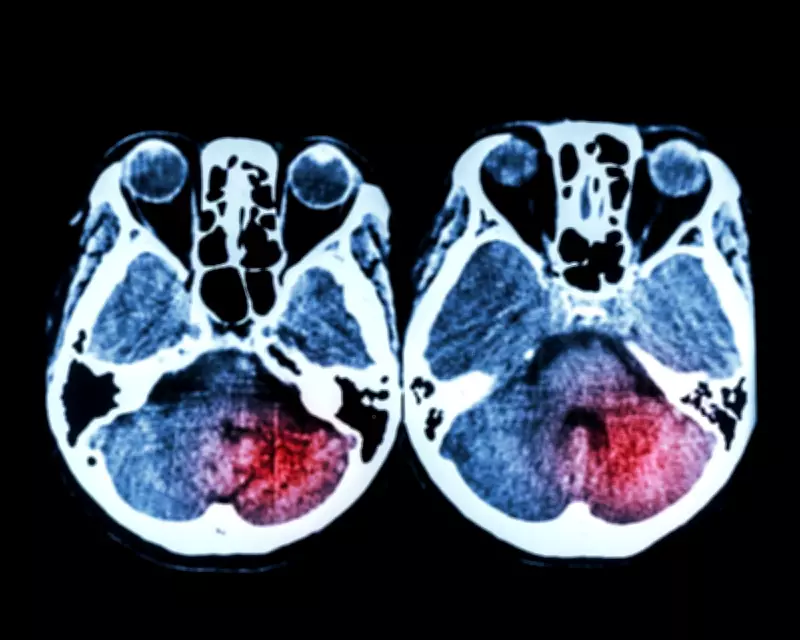

Thrombectomy, a minimally invasive procedure where doctors remove clots via catheter, is crucial for severe strokes caused by blocked brain arteries. The NHS invests over £100 million annually in this treatment, viewing it as vital to reducing the 113,000 avoidable deaths from major conditions like heart disease and cancer in England.